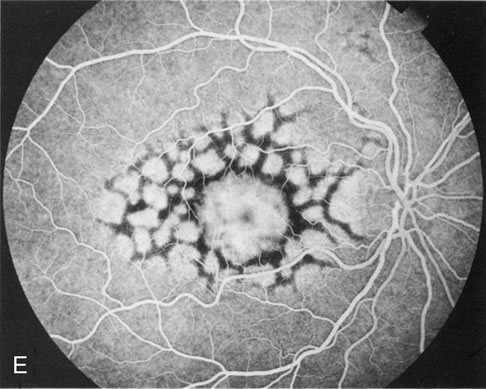

Fig. 6. Generalized choroidal dystrophy. This 65-year-old woman gradually developed enlarging, progressive areas of choroidal atrophy over a 20-year period. When initially seen, the abnormalities were confined to the peripapillary and macular region (A,B). In a recent examination, the generalized choroidal atrophy is vividly demonstrated on angiography (C–F).

Fig. 7. Central areolar choroidal dystrophy. The presence of choroidal atrophy in this well-circumscribed macular lesion (A) is confirmed by persistent visualization of the larger choroidal vessels as seen on angiography (B). Peripapillary (pericentral) choroidal dystrophy. The areas of choroidal atrophy are well-demarcated and contrast with the areas of normal choroid (C, D). Crystalline retinopathy (of Bietti). The areas of choroidal atrophy correspond to areas of the retina where crystals are not present (E, F).